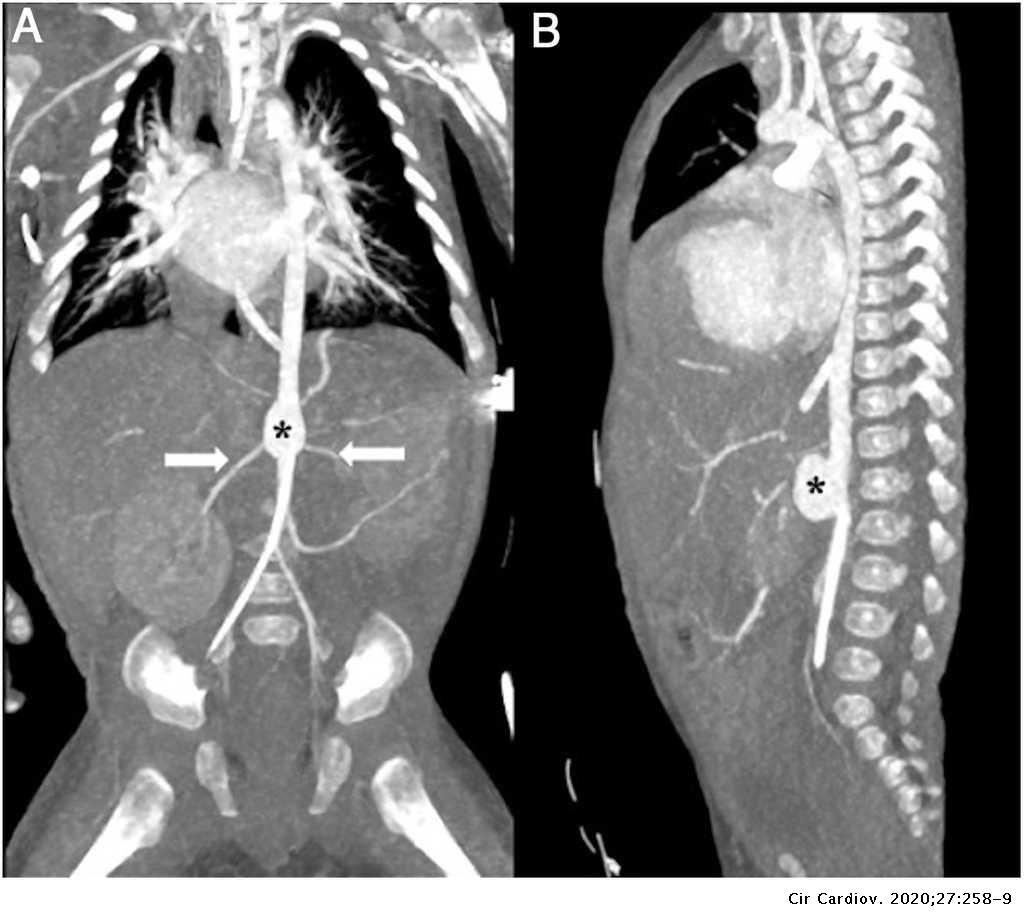

Así se interviene el aneurisma de aorta abdominal roto La Verdad

Source: www.laverdad.es

Aneurisma de la aorta abdominal en un lactante Cirugía Cardiovascular

Source: www.elsevier.es